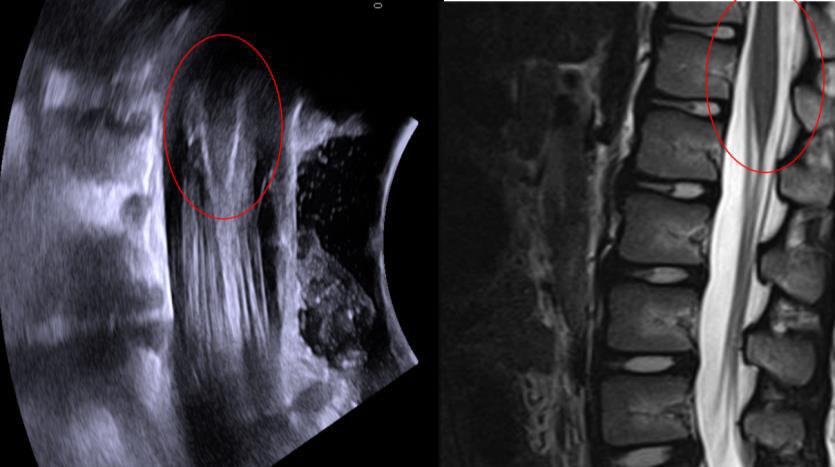

SDR involves surgically accessing the spinal cord (typically in the lumbosacral region, L2 to S1 or S2).The dorsal (sensory) nerve roots are carefully identified and then divided into smaller bundles called rootlets.